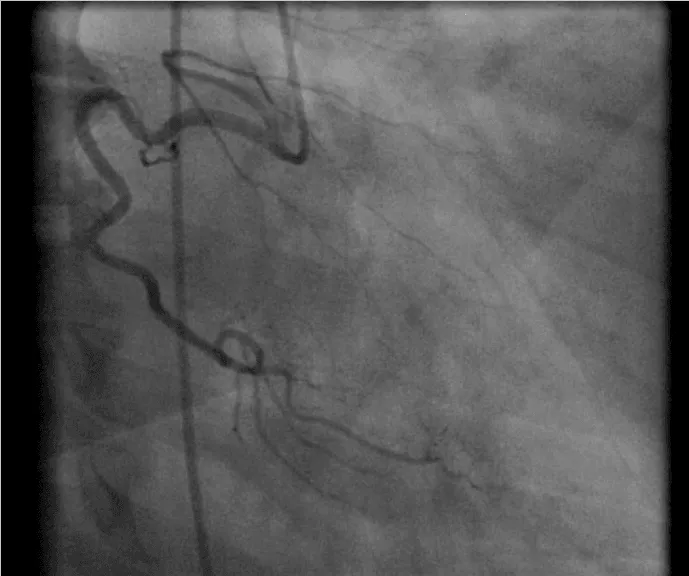

Her initial vital signs upon presentation to the hospital were; blood pressure: 161/76 mm Hg, heart rate: 96 beats per minute, respiratory rate: 27 breaths per minute. Physical exam revealed a cardiac auscultation findings of a grade 2 diastolic murmur which was loudest at the 2nd right intercostal space as well as a grade 2 systolic flow murmur. Cardiac biomarkers were elevated with initial troponin-I of 0.33 ng/mL, peak of 2.28 ng/mL and subsequent down trend. Electrocardiography (Figure 1) showed sinus rhythm with anterior and inferolateral T wave inversion and chest radiograph (Figure 2) was unremarkable. She underwent coronary angiography which revealed normal coronary arteries. The takeoff of the right coronary artery (RCA) was noted to be superior and anterior to its normal position (Figures 3A and 3B). Transthoracic and transesophageal echocardiography (TEE) revealed normal left ventricular systolic function and severe insufficiency of the aortic valve with Quadricuspid morphology (Figure 4A in Diastole, Figure 4B in Systole, Figure 4C Long Axis of the aortic valve). She underwent aortic valve replacement with a # 19mm ON-X mechanical valve. Intraoperatively it was noted that the ostium of the right coronary artery was over the aberrant leaflet. Her postoperative course was complicated by the development of supraventricular tachycardia, posteriorly localized pericardial effusion, severe hemolytic anemia, renal failure and pancreatitis leading to her death eleven days after the surgery.

Figure 3a: Left anterior oblique View of the RCA.

Figure 3b: Right anterior oblique view of the RCA.

In our case as we described, the QAV was noted to have three equal sized cusps and one larger cusp and is a type E valve according to the 1973 Hurwitz and Roberts’s classification [4]. Congenital QAV predisposed her to the development of severe AI and was associated with the finding of an anomalous origin of the right coronary artery. The RCA originated from the right dorsal or posterior cusp of the aortic valve and the left main coronary artery originated from the left ventral or anterior cusp, nomenclature of the cusp orientation is as proposed by Fernandez et al. [13]. In their study of quadricuspid aortic valves in Syrian hamsters [13]. The supernumerary cusp was identified as the right dorsal cusp and the RCA originated from that corresponding right dorsal sinus which was identified intraoperatively. Although the presence of the patient’s comorbidities such as uncontrolled HTN, obesity and recurrent pancreatitis did not have a causal relationship with the finding of QAV or the development of severe AI, they likely played a role in her post-surgical mortality.